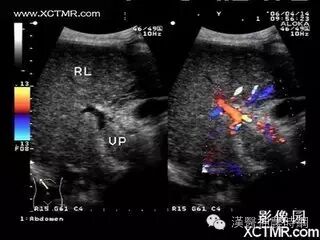

1.超声检查  B超检查用于肝癌诊断具有无损伤、无放射损害、简便、价廉、敏感度高、可重复性等优点。它可显示肿瘤的大小、形状、部位、肿瘤与血管的关系以及肝静脉、门静脉有无癌栓等,其诊断符合率可达90%。B超可检出1~2cm的小肝癌,最小直径为0.5~0.7cm。文献报道高分辨力B超对0.5~2.0cm的肝内微小灶的发现率较高,但定性诊断的准确率仅为58%。

近年国内外均有人采用超声对比剂,如铁或钆等行声学造影,有助于定性诊断和确定病灶大小。原发性肝癌B超图像常显示肝体积增大,病变向肝表面隆起,周围常有声晕等。其回声可表现为低回声型、高回声型和混合回声型。小肝癌常呈低回声型,大肝癌或呈高回声,或高低回声混合,并可见中心坏死液化的无回声区。B超检查可因肺、胃等器官遮盖存在盲区,造成遗漏病变,如右膈下、左外叶上段等。微小病变位于肝实质深部并伴有严重肝硬化时,常难以辨认。另外与操作者的经验和检查是否细致均有关。